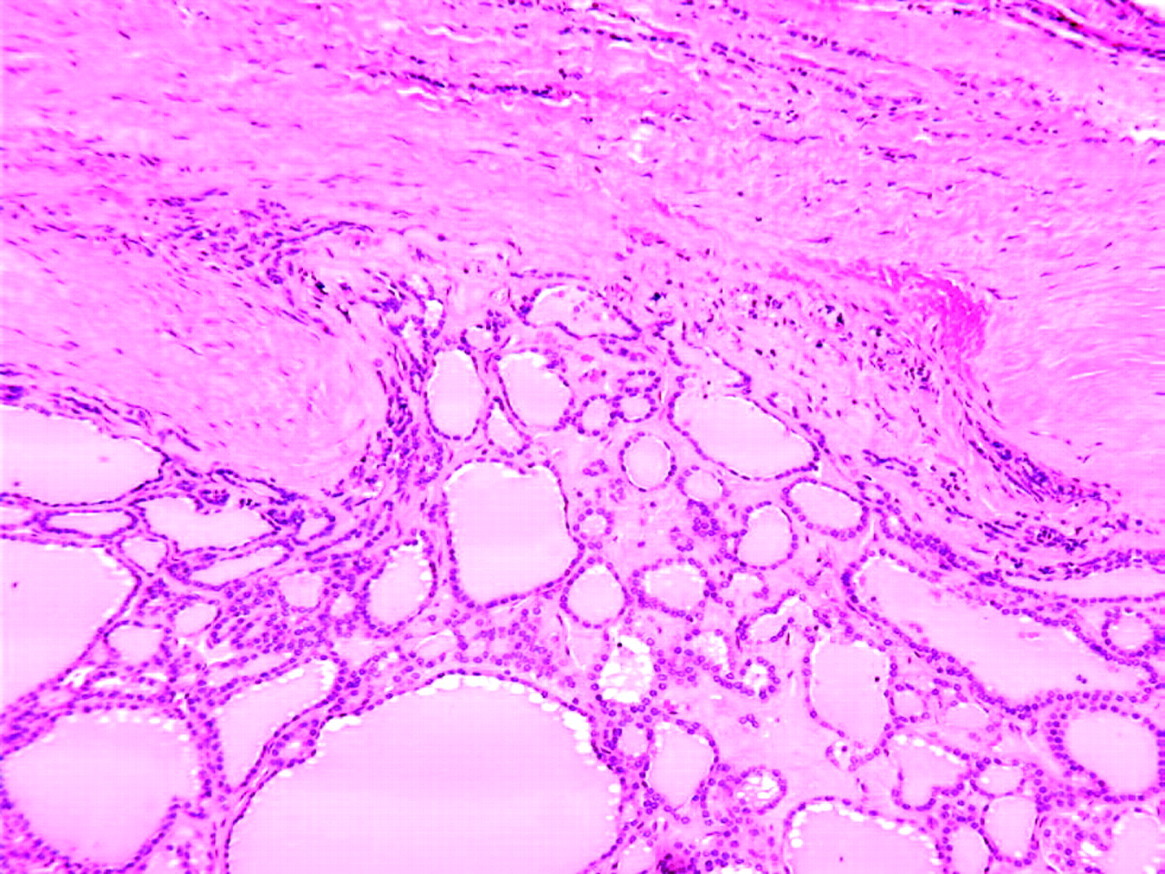

Tx for this dx on thyroid FNA

Note the Hurthle cells, indicating possible Hashimoto thyroiditis or adenoma. Note that you cannot make a definitive dx of Hurthle cell or follicular carcinoma (shown below) on FNA and lobectomy is appropriate with total thyroidectomy if cancer is present. If thyroiditis, hormone replacement alone is fine.